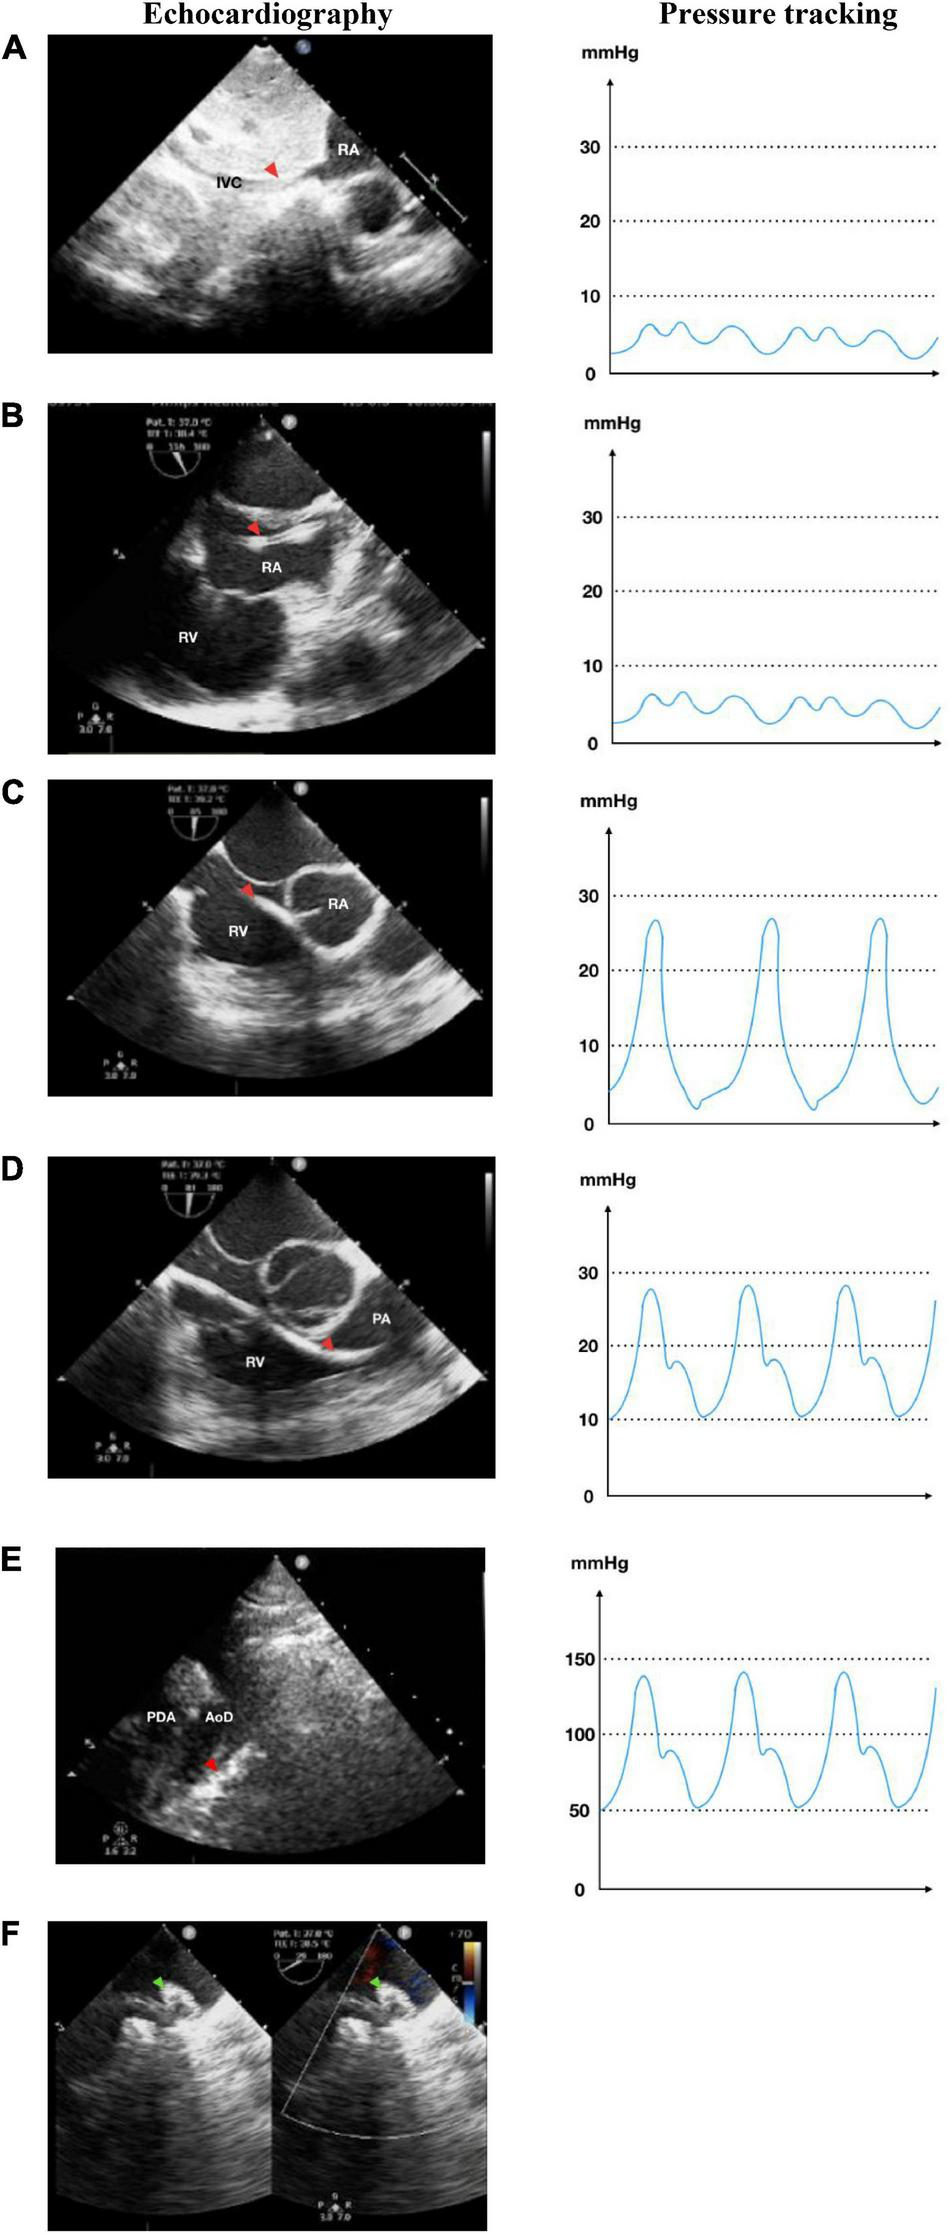

FIGURE 2

Antegrade transvenous approach of percutaneous patent ductus arteriosus (PDA) closure. (A) Catheter is seen in IVC in transthoracic echocardiography (TTE) subxiphoid view. (B) Catheter is seen in RA in TEE bicaval view (90–110°). (C) Catheter in RV TEE 90° view. (D) Catheter enters PA in TEE 90° view. (E) Catheter crossed from PA towards AoD through PDA in TTE arch view. (F) The device is stowed in place in TEE (40–50°). IVC, inferior vena cava; RA, right atrium; RV, right ventricle; PA, pulmonary artery; Ao, aorta; LA, left atrium; LV, left ventricle; AoD, descending aorta; PDA, patent ductus arteriosus. Red arrowhead shows the catheter head. Green arrowhead indicates the occluder device.

In this study, we compared the time taken for PDA closure procedures using fluoroscopy and echocardiography. The median procedural time of using both antegrade and retrograde approaches for the test and control groups was insignificant (p = 0.575). The retrograde approach had a shorter procedural time in comparison to the antegrade approach where the catheter needs more manipulation to be directed into the right ventricle and PA to reach the PDA (see Figures 2C,D). However, the retrograde approach is limited to patients with low body weight or large PDA since complications might occur through arterial access, such as thrombosis at the access site. Regardless of the approach, the difference in procedural time between the echocardiography group and the fluoroscopy group was insignificant (p = 0.09). These results mean that using only echocardiography did not compromise procedural time.